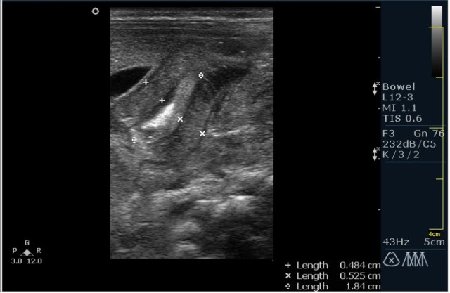

Ребёнок 1 месяц 10 дней от родy, с отсуствием прибавки в весе.

Hypertrophic pyloric stenosis.

Criteria:

1.Pyloric channel > 12 mm in length

2.Muscular layer thickness > 3-4 mm

3.Donuts sign at transverse scanning